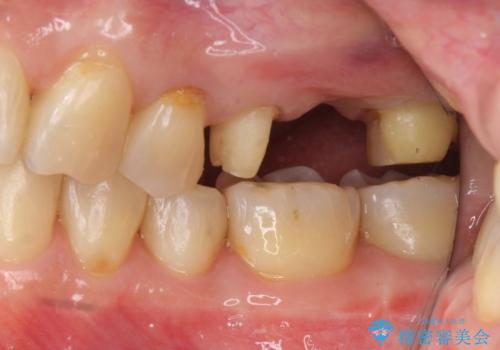

奥歯も少なく、左上奥歯はブリッジにすることになりました。

左下の前歯を中に入れるスペースを確保する目的で左下の奥歯を後ろ移動させました。

右上大臼歯2本の欠損については、インプラント治療をお勧めしましたが、ご希望によりそのままとなりました。